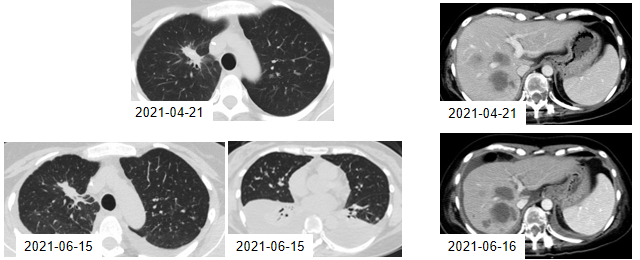

图12. 2021年4月21日与6月15日的CT检查结果

★ 五线治疗——峰回路转,伏美替尼持续治疗中

2021年6月15日,患者开始口服伏美替尼(160mg po 1/日)。伏美替尼治疗4周后胸腔积液较前吸收,肝脏转移病灶较前缩小,目前患者仍在持续口服伏美替尼。

图13. 2021年6月与7月的CT检查结果